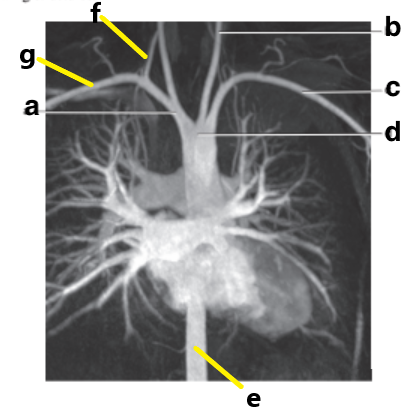

What is letter e?

Subclavian artery

What is letter f?

Vertebral artery

What is letter a?

What is letter c?

Aortic arch

Which letter is the left common carotid?

a

Abdominal aorta

Which letter is the Right vertebral artery?

f

Carotid bifurcation

Common carotid artery

What is letter b?

Basilar artery